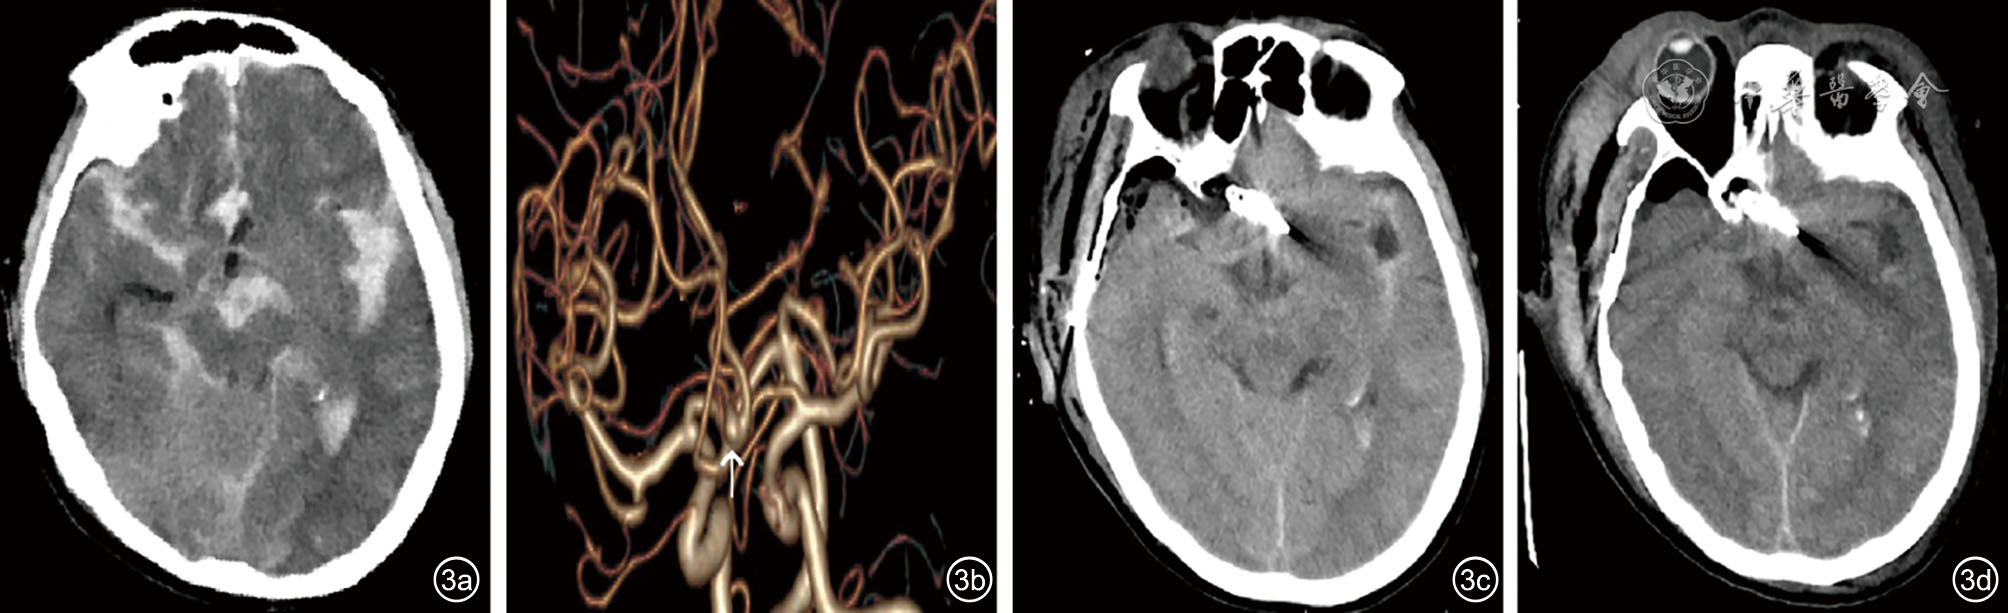

图3 病例3影像资料。图a:入院CT显示较厚的SAH,伴脑室内出血;图b:CTA显示前交通动脉动脉瘤(箭头);图c:术后当天CT显示SAH、脑室内出血较前有所吸收;图d:术后第3天,在PSH发作后立即复查CT,较几小时前的CT无明显变化,仍可见广泛脑水肿 注:SAH 为蛛网膜下腔出血;CTA 为CT 血管造影;PSH 为阵发性交感神经过度兴奋